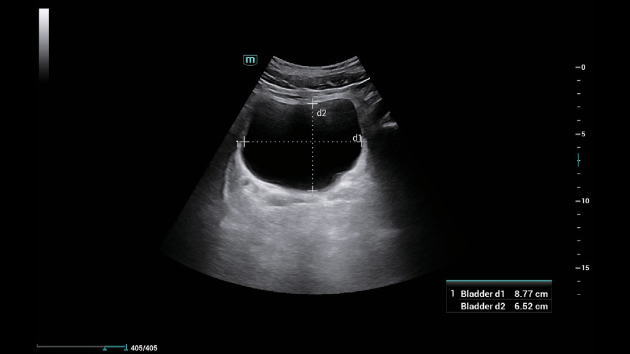

A linha Consona apresenta solu??es inovadoras e eficientes que o ajudam a realizar diagnÃģsticos em diversos tipos de pacientes.

N?o importa se sua rotina ÃĐ em hospitais, clÃnicas ou se vocÊ estÃĄ aprimorando habilidades em Imagem Geral, SaÚde da Mulher ou na ÃĄrea Cardiovascular; vocÊ encontrarÃĄ ferramentas altamente poderosas disponÃveis para manter-se na vanguarda.

Solu??es abrangentes de imagens com tecnologia ZST+

A plataforma ZST+ ÃĐ uma inova??o extraordinÃĄria, representando a evolu??o do ultrassom. Transformando as mÃĐtricas de ultrassom: da forma??o convencional do feixe ao processamento baseado em dados de canais. Supera a limita??o de compensa??o tradicional entre resolu??o espacial, resolu??o temporal e uniformidade de tecido, oferecendo qualidade de imagem excepcional para solu??es de imagem infinitas com melhorias inigualÃĄveis.